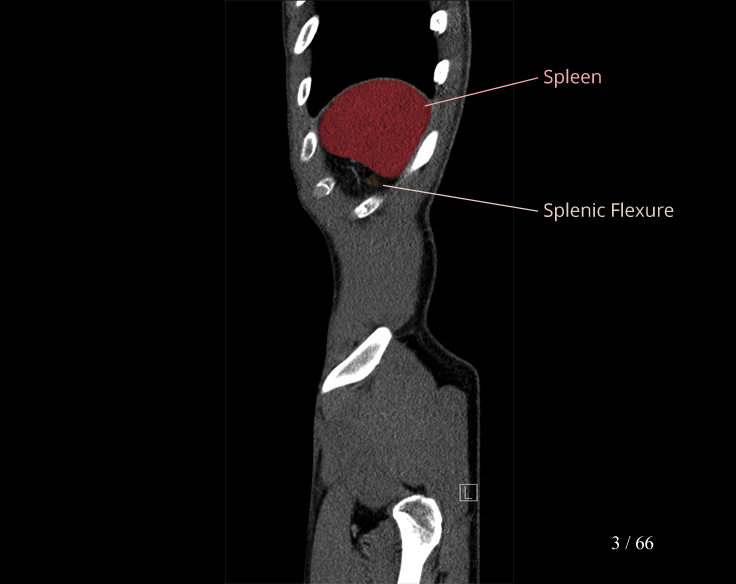

Body

Covers abdominal CT anatomy.